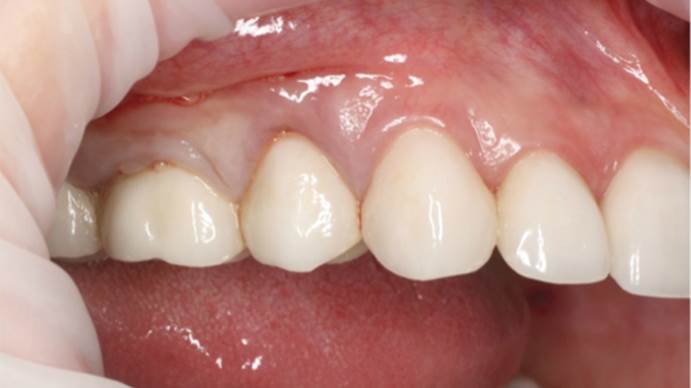

Clinical case: Extraction, immediate implant placement, & provisionalization

- Courtesy of Dr. Iulian Filipov, Romania -

Keywords

AnyRidge, R2GATE, guided surgery, immediate placement, immediate provisionalization, initial stability, Dr. Iulian Filipov, #25, maxillary posterior, immediate loading, Mega ISQ